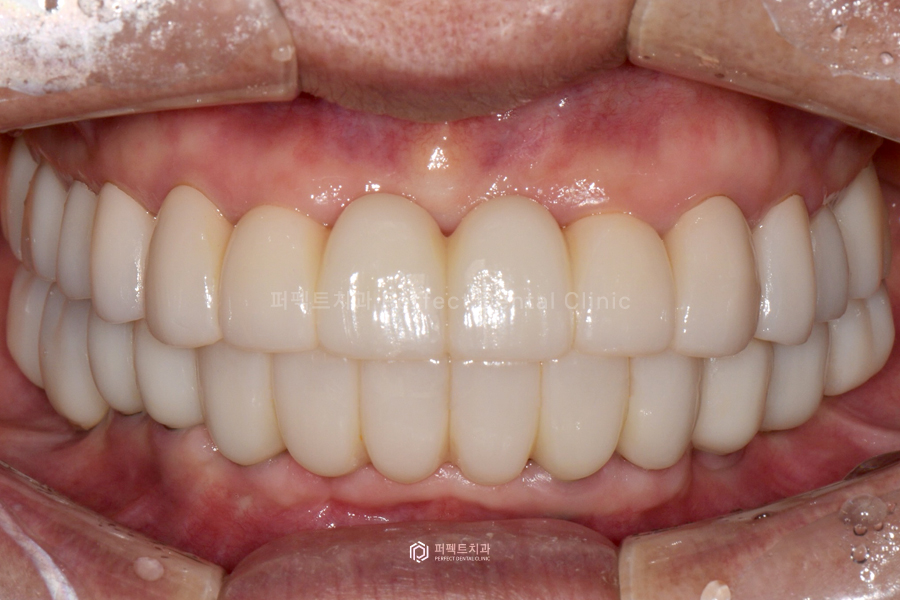

보철까지 모두 완성한 사진입니다. 굉장히 예쁘게 완성이 되었고, 환자분도 결과에 만족하셨습니다.

위 사진을 보시면 전체 신경치료 후 지르코니아 크라운을 씌웠고, 아래는 임플란트 10개를 식립 후 위에와 마찬가지로 지르코니아 크라운으로 완성을 했습니다.